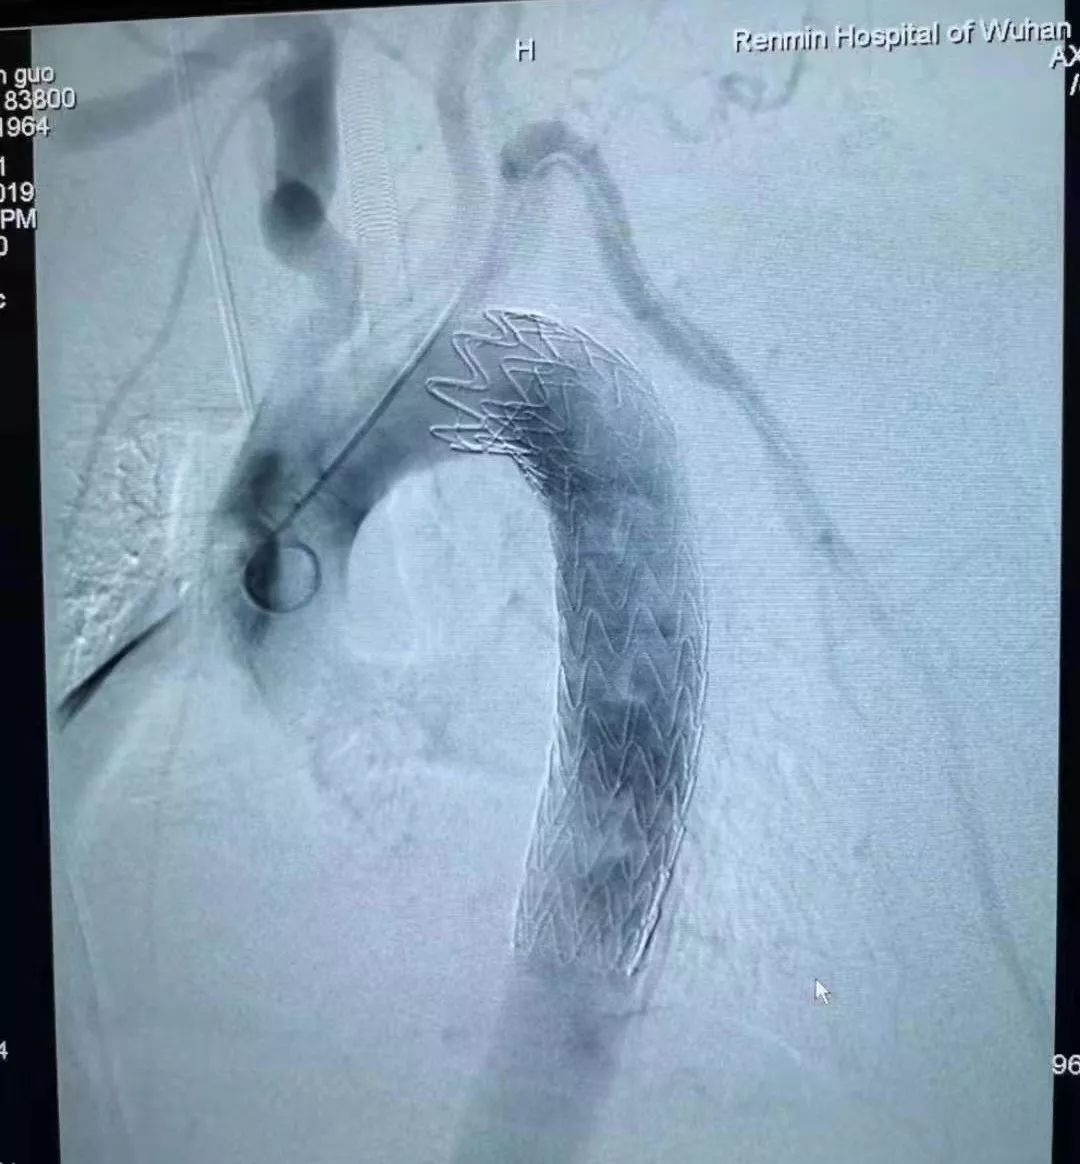

经过详细讨论,专家团确定了微创取刺手术方案:先由心血管外科专家为林先生植入主动脉支架堵住血管缺口,再由消化内科专家尝试进行消化内镜下微创取刺。

在麻醉医师保驾护航下,心血管外科团队顺利将主动脉支架植入林先生体内,将已经开始糜烂的血管缺口堵牢。随后,消化内科团队开始尝试进行消化内镜下取刺。